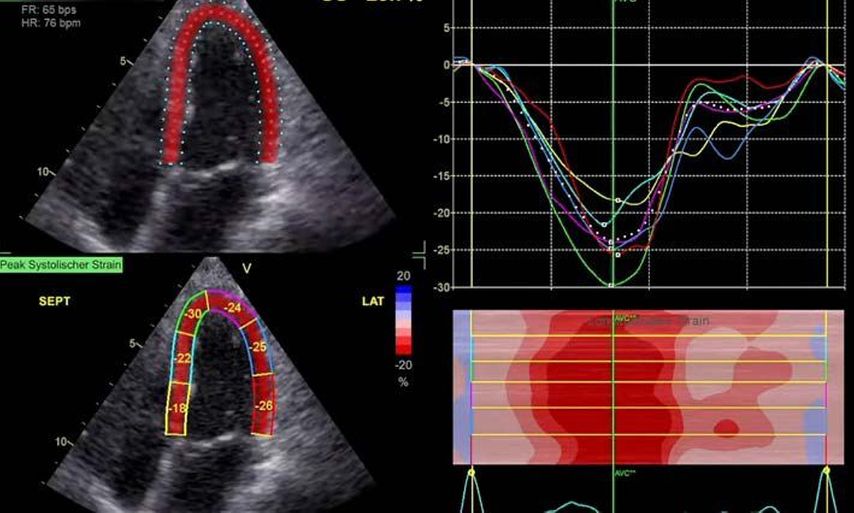

Die moderne Echokardiografie bietet die Möglichkeit einer hämodynamischen Evaluation in Ruhe wie auch bei „point-of-care“-Belastung. „Strain imaging“ und „myocardial work“ können neben bekannten Parametern, wie der Ejektionsfraktion (EF) und der Myokardmasse, ergänzend zur Diagnostik von Herzerkrankungen beitragen.

Im Echolabor des Pyhrn-Eisenwurzen Klinikums Steyr wird jede Form der Myokardwandverdickung mittels einer vollständigen Standardechokardiografie untersucht.2 Dabei wird auch ein Fokus auf die kontrastmittelunterstützte Sonografie gelegt, um die tatsächliche Dicke des Myokards zu vermessen.3 Die Verdickung sollte optimalerweise mittels 3D-LV-Massenmessung erfolgen. Die Messung im 2D-Bild ist dahingehend unterlegen. Ebenso wird jede Myokardwandverdickung mittels 2D-„strain imaging“ in der transthorakalen Echokardiografie (TTE) untersucht.4–6 Der „strain“ ist eine Messung der longitudinalen Funktion des Herzens (Video 1).

Der erste Fall beschäftigt sich mit einem Patienten mit einer hypertrophen Kardiomyopathie (HCMP). Er gibt eine deutliche Belastungsdyspnoe sowie einen ausgeprägten Leistungsknick an. Es wurde infolgedessen eine Untersuchung mittels standardisierter Echokardiografie inklusive „strain imaging“ durchgeführt. Der globale longitudinale „strain“ (GLS) mit –16% in Ruhe war gering reduziert. Es konnte kein relevanter LVOT-Gradient in Ruhe nachgewiesen werden. In der Belastungssituation (Handgrip, Valsalva, Kniebeugen und als Vorbereitung zur Untersuchung ein ausgiebiges Frühstück und Kaffee sowie ein am Vorabend konsumiertes Bier) konnte bei Kniebeugen mit einer Herzfrequenz von 126/min ein Spitzengradient bis 52mmHg dargestellt werden. Somit ergibt sich die Diagnose einer HOCMP mit einem belastungsinduzierten Gradienten. Bei bereits bestehender und ausgereizter Therapie unter Betablocker besteht die Indikation zur Therapie mittels des kardialen Myosininhibitors Mavacamten (Klasse-IIa-Empfehlung laut ESC).1 Darunter verbesserte sich die klinische Situation des Patienten deutlich, der Patient konnte uneingeschränkt Sport ausüben. Über die Zeit kam es zu einer geringen Reduktion der LV-Masse und einer geringen Zunahme des LV-„strain“. Die Belastungssituation zeigte durchwegs normale „strain“-Werte mit –20% (mit regionaler Reduktion bei Myokardwandverdickung im Sinne einer Hypertrophie). Die myokardiale Arbeit beim konkreten Patientenfall ist ebenso in Ruhe im grenzwertigen und unter Belastung im guten Normalbereich.6,8,9 Der Patient ist derzeit unter 5mg Mavacamten einmal täglich optimal eingestellt. Die EF in Ruhe ist konstant bei 50–55%. In Video 2 werden unterschiedliche Gradienten dargestellt, um eine HOCMP mit LVOTO von z.B. einer Mitralklappeninsuffizienz zu unterscheiden.Die Verdachtsdiagnose wurde mithilfe der Echokardiografie gestellt und durch das septal betonte „patchy“ LGE im MRT bestätigt.1,5

Andere Formen der Myokardwandverdickung, die mit „strain“ und MRT gut dargestellt werden können, sind einerseits die Differenzierung der Auswirkung der arteriellen Hypertonie (weiblich, 72a) bei Vorliegen einer Herzinsuffizienz mit normaler EF, einem GLS von –15,4%, einem LA-„strain“, in Reservoirphase 25% bei gering verlängerten T1-Zeiten im MRT. Andererseits kann Steroidabusus (männlich, 44a) zu einem reduzierten „strain“ mit gering verlängerten T1-Zeiten und einer Normalisierung der bildgebenden Befunde nach 2 Jahren nach Absetzen führen bzw. eine Mitochondriopathie (männlich, 32a) zu einer unklaren Myokardverdickung mit diffus reduziertem „strain“ und reduzierter LV-Funktion.4,11,12